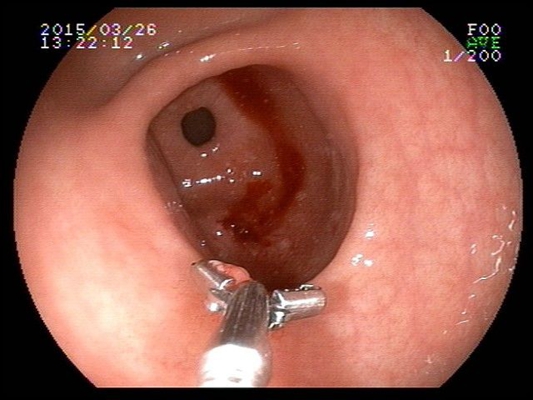

食道炎圖片